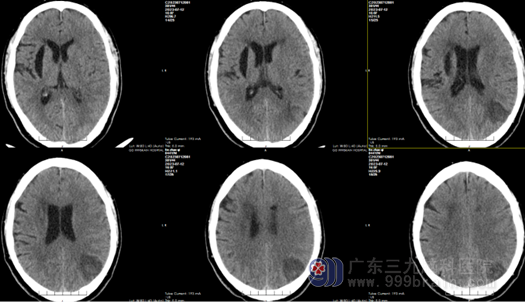

(术前CT)

我院神经外十科主任欧阳辉教授接诊患者后。详细询问其病史,结合患者颅脑MR 结果,初步确定为低级胶质瘤,欧阳辉教授带领团队进行了详细术前讨论与评估。经多方因素综合考虑,最终确定了手术方案。向家属明确告知手术必要性和风险,获得充分理解并签字同意后,7月14日,送手术室全麻下行左侧顶枕叶胶质瘤切除术+硬脑膜修补+颅骨成形术”,手术顺利,术后病理结果提示为弥漫性胶质瘤,WHO分级:2级。低级别胶质瘤常以癫痫发病,林叔手术后再也没有发作癫痫。